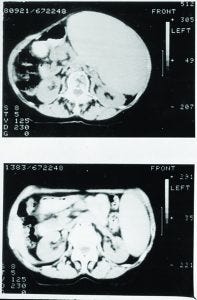

Figure 2: Treatment of non-Hodgkin’s lymphoma (NHL) with Campath-1H

Eventually, Campath-1G was humanized, and the resulting Campath-1H progressed into the clinic from our laboratory. In a patient with end-stage lymphoma, in whom lymphoma cells had spilled out into the blood (similar to leukemia), Campath-1H depleted those cells effectively (Figure 2).